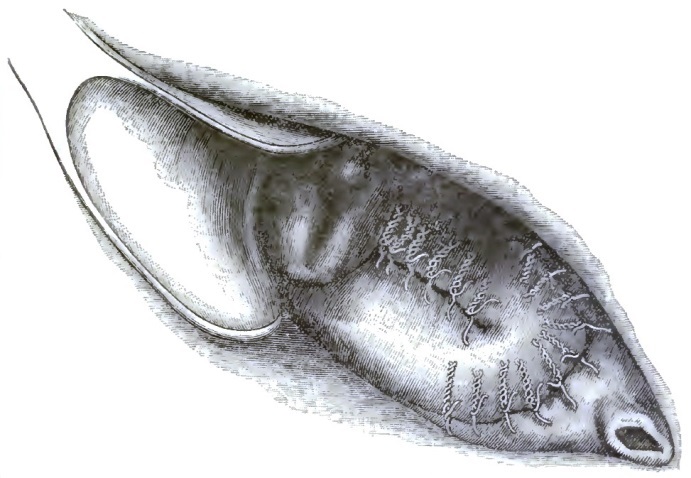

| 28. | FOLLICULAR VULVITIS (HUGINER) |

| 29. | ABSCESS OF GLANDS OF BARTHOLINI |

| 30. | ELEPHANTIASIS OF VULVA |

| 31. | ELEPHANTIASIS OF VULVA |